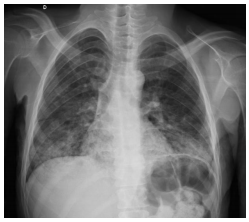

Qual patologia placentária está representada na figura abaixo?